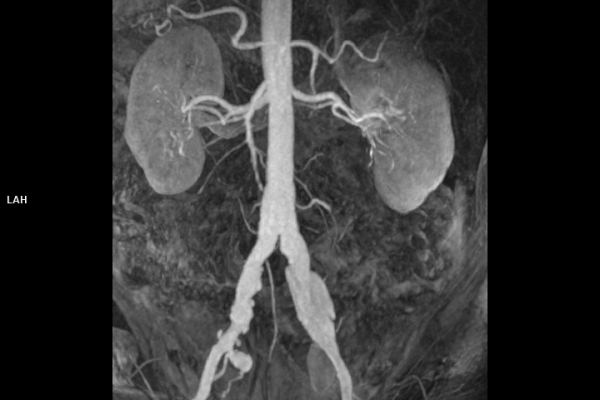

• Gefäßdiagnostik (CT-Angiographie)

Wir bieten ein breites Spektrum an Untersuchungen an, von Standarduntersuchungen der Gelenke, Organe oder großflächigen Körperregionen bis zu Spezialuntersuchungen zum Beispiel des Herzen oder der Gefäße. Zusätzlich werden Angiographien (Darstellung von Blutgefäßen), Endometriose-Abklärungen und Mamma-Untersuchungen durchgeführt. Genauere Details können Sie der MRT/CT-Übersicht und der Preisliste entnehmen, oder Sie wenden sich direkt an unser Team, das Sie gerne zur passenden Untersuchung berät.

Die MRT (Magnetresonanztomographie) arbeitet mit Magnetfeldern und Radiowellen und eignet sich besonders für Untersuchungen der Weichteile wie Gehirn, Muskeln oder Gelenke. Die CT (Computertomographie) nutzt Röntgenstrahlen und liefert schnelle, hochauflösende Bilder, insbesondere für Knochen, Lunge oder innere Organe. Die Wahl der jeweiligen Untersuchung richtet sich an das individuelle Krankheitsbild und wird bei der Überweisung festgelegt.